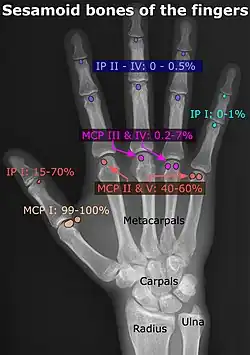

Sesamoid bones can be found on joints throughout the human body, including:

- In the hand—two sesamoid bones are commonly found in the distal portions of the first metacarpal bone (within the tendons of adductor pollicis and flexor pollicis brevis). There is also commonly a sesamoid bone in distal portions of the second metacarpal bone and fifth metacarpal bone.[7]